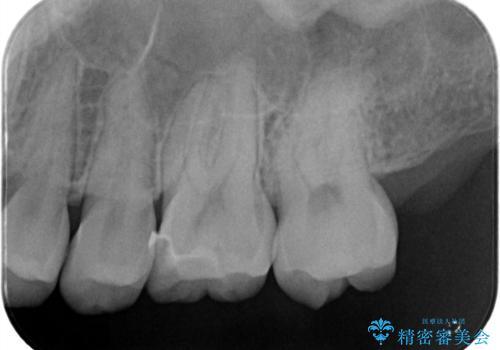

- 定期検診で虫歯が見つかった患者様です。ハイブリッドインレーで治療を行いました。

定期検診で虫歯が見つかった患者様です。

ハイブリッドインレーで治療を行いました。

ハイブリッドインレーはセラミックインレーとは違い、セラミックとプラスチックの混合物です。保険治療の材料よりは優れていますが、プラスチックが混ざっている分、セラミックインレーには劣ります。型取りの材料はセラミックインレーの時と同様のシリコン印象材を使用しています。